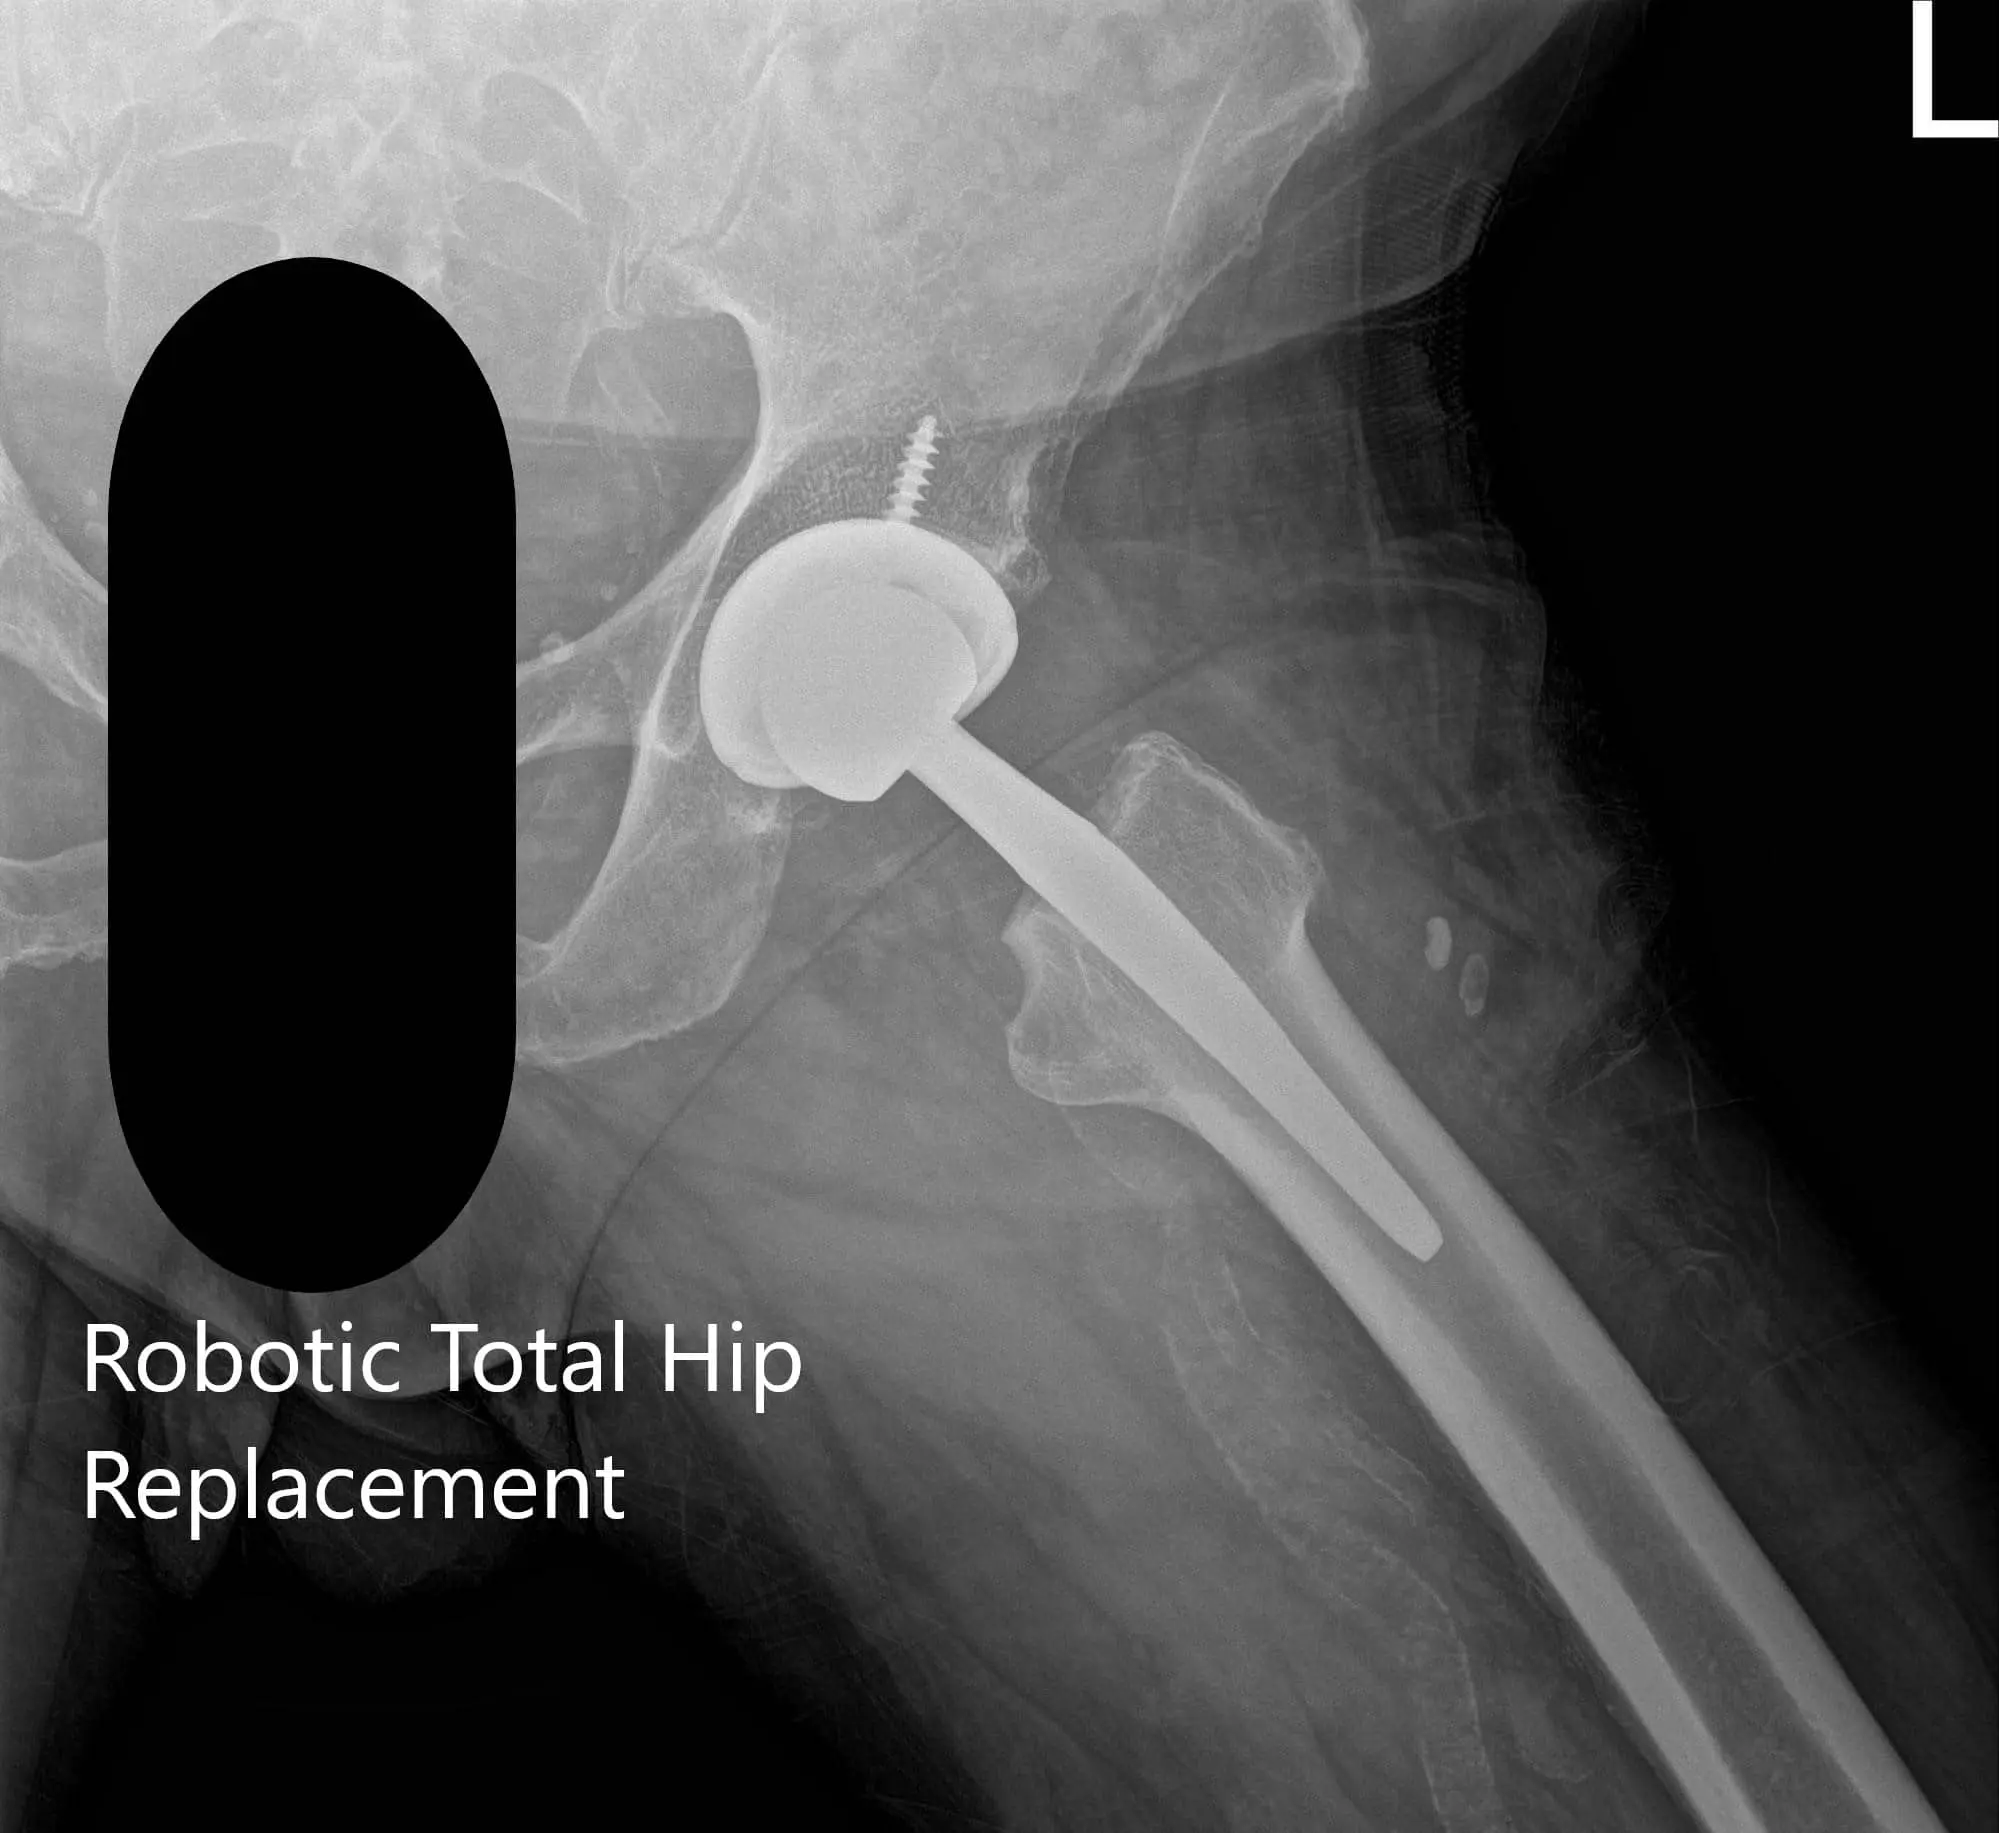

Postoperative X-ray of the left hip showing AP and frog-legged lateral view

Postoperative X-ray of the left hip showing AP and frog-legged lateral view - img 2